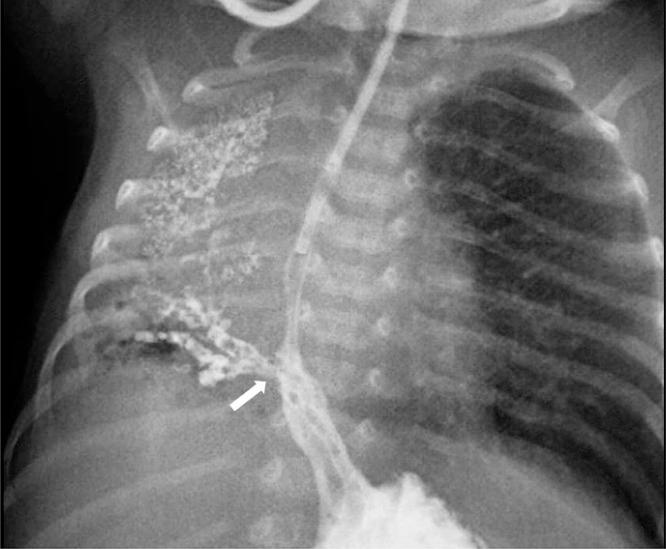

Esophageal lung is a rare communicating bronchopulmonary foregut malformation in which the main bronchus arising from the trachea is absent. The affected lung is usually hypoplastic and aerated via an anomalous airway originating from the esophagus. Other anomalies such as esophageal atresia with tracheoesophageal fistula or VACTERL (vertebral defects, anal atresia, cardiac defects, tracheoesophageal fistula, renal anomalies, and limb abnormalities) association can co-exist. The initial radiographic findings may be normal, but subsequent imaging usually shows progressive and recurrent lung collapse, probably because of recurrent aspiration through the anomalous airway and poor compliance of the affected lung during breathing. In this report, we describe a neonate with esophageal lung and rare associated anomalies, including anorectal malformation, pulmonary artery sling, and inferior vena cava interruption with azygous continuation. To our knowledge, this is the first report of esophageal lung with such associations.

食管肺是一种罕见的交通性支气管肺前肠畸形,其中起源于气管的主支气管缺如。患侧肺通常发育不全,并通过起源于食管的异常气道进行通气。其他异常情况,如食管闭锁合并气管食管瘘或VACTERL(脊柱缺陷、肛门闭锁、心脏缺陷、气管食管瘘、肾脏异常和肢体异常)综合征可能同时存在。最初的影像学表现可能正常,但随后的影像学检查通常显示进行性和复发性肺不张,这可能是由于通过异常气道反复误吸以及患侧肺在呼吸时顺应性差所致。在本报告中,我们描述了一名患有食管肺及罕见相关异常的新生儿,这些异常包括肛门直肠畸形、肺动脉吊带以及下腔静脉中断伴奇静脉延续。据我们所知,这是首次报道伴有此类关联的食管肺病例。